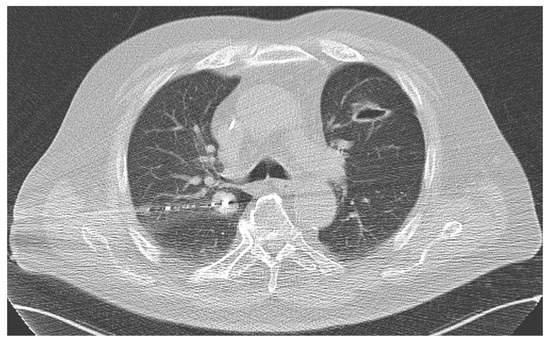

2.7. MWA Procedure